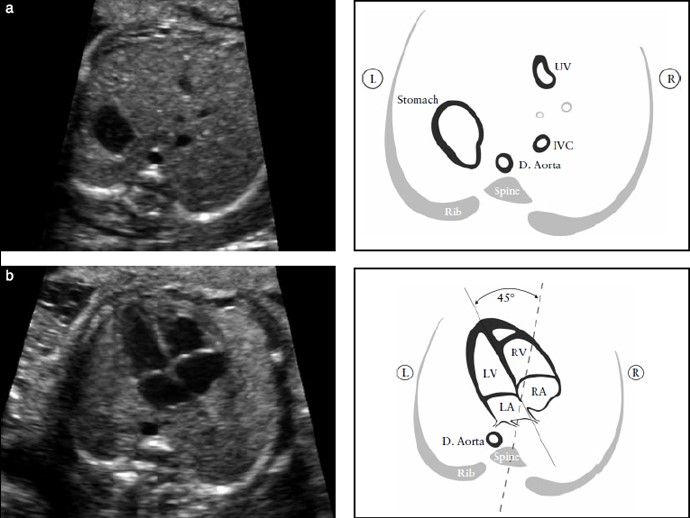

Рисунок 1. (А) Поперечный срез живота плода: определение ситуса. После определения положения плода в утробе матери необходимо идентифицировать желудок плода в левой стороне живота; там же, где видна нисходящая аорта (D. Aorta) – слева, и нижняя полая вена (IVC) – справа от позвоночника. Короткий сегмент пупочной вены (UV) также должен визуализироваться. (b) Направление оси сердца: сердце большей частью должно находиться в левой половине грудной клетки.

Верхушка сердца должна быть 45º по отношению к передне-задней оси грудной клетки. LA- левое предсердие, LV- левый желудочек; R- право; RA- правое предсердие; RV-правый желудочек.

Если сердце и/или желудок плода не определяются с левой стороны, то это подозрительно на аномалии расположения органов (ситуса) – situs abnormalities. Аномальная ось сердца увеличивает риск ВПС, особенно выходных трактов. Такая находка может так же ассоциироваться с хромосомными аномалиями.

Смещение сердца от его нормального левостороннего расположения может быть вызвано также диафрагмальной грыжей или объемным образованием, таким как кистозная аденоматозная мальформация легких. Нарушения положения сердца также могут быть вторичными при гипоплазии или агенезии легкого плода. Сдвиг оси сердца влево может также быть в следствие гастрошизиса или омфалоцеле.